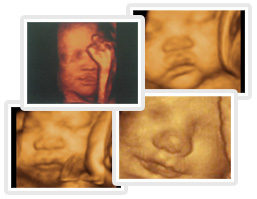

名词解释(三维动态彩超):三维动态彩超就是四维成像技术(4D),能直观、立体显示人体器官的三维结构及动态、实时地观察立体结构,而以往的二维成像技术只能显示人体器官的某一切面。传统的三维彩超是静态地观测胎儿,不能刻盘,而三维动态彩超是动态的,能自动为胎儿拍摄动态录像,不仅能让您感受到宝宝的呼吸和运动,还能亲眼目睹到胎儿乖巧的面容和一举一动的表现。

多媒体、数码应用:可以将宝宝的样子和动作制作成照片或VCD,让宝宝拥有最完整的0岁相册,这已经不再是幻想。